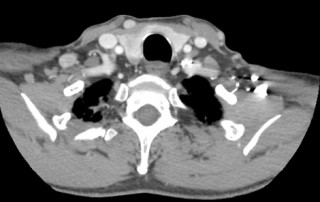

Scanner thorax abdomen pelvien : masse médiastinale antérieure et supérieure, absence d’atteinte du pédicule vasculaire, absence de nodule pulmonaire, scanner sous-diaphragmatique normal. Cible médiastinale taille 94 x 67 mm